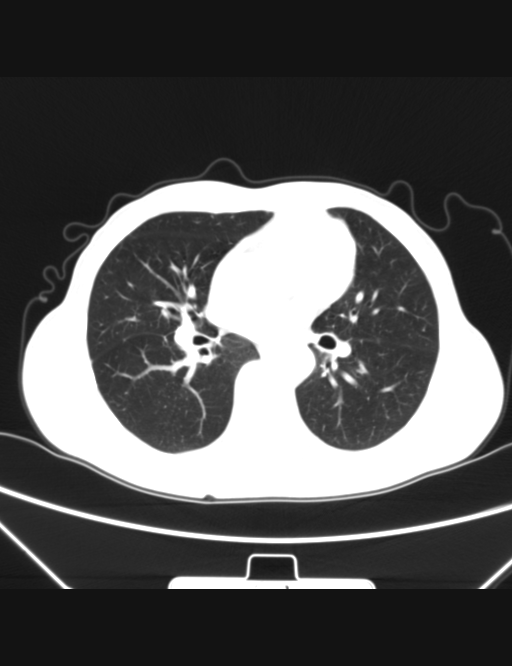

胸部ct平扫图片,金典=== - 医学影像学讨论版 - 爱爱医医学论坛

图片尺寸512x666

请专家会诊胸部ct片 - 医学影像学讨论版 - 爱爱医医学论坛

图片尺寸1544x1030